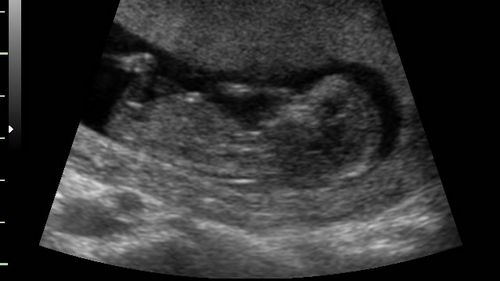

• УЗД. Призначається не всім вагітним. Встановлюється факт вагітності, визначається кількість ембріонів і їх місце розташування (з метою своєчасно виявити позаматкову вагітність).

УЗД 2 місяці вагітності (фото)